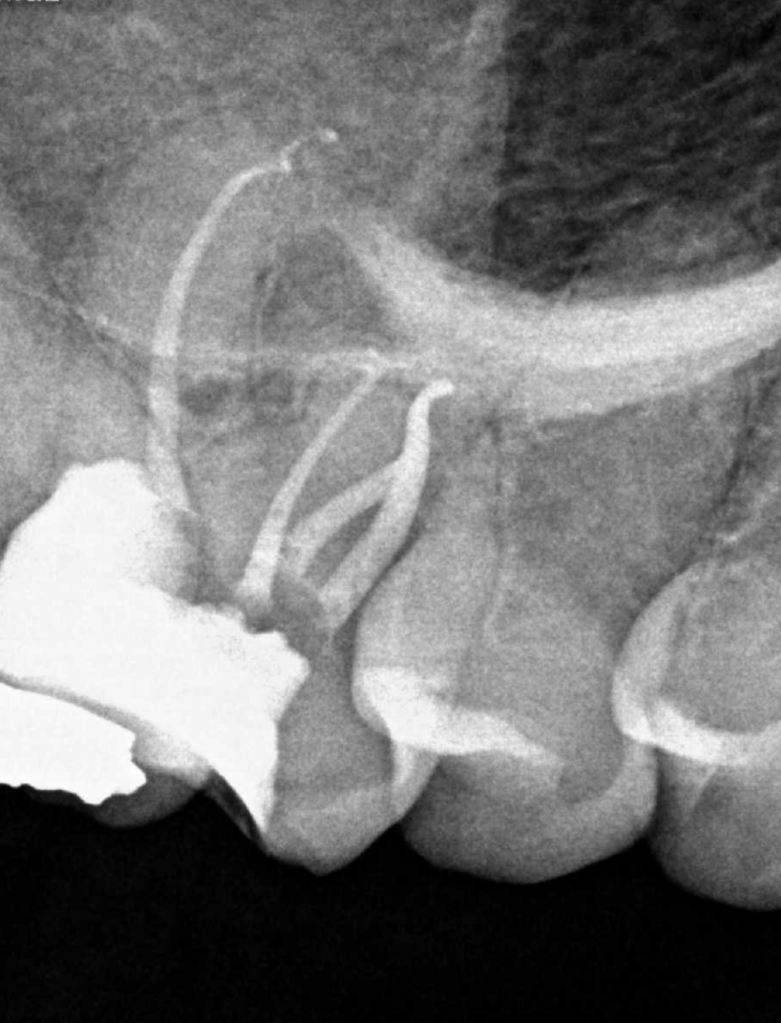

Pulpotomía biodentine + reco preendio